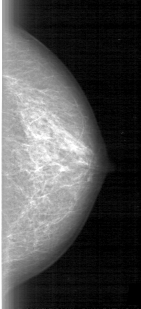

D_4012_1.RIGHT_MLO

LEFT_MLO LINES 5386 PIXELS_PER_LINE 2341 BITS_PER_PIXEL 12 RESOLUTION 43.5 NON_OVERLAY